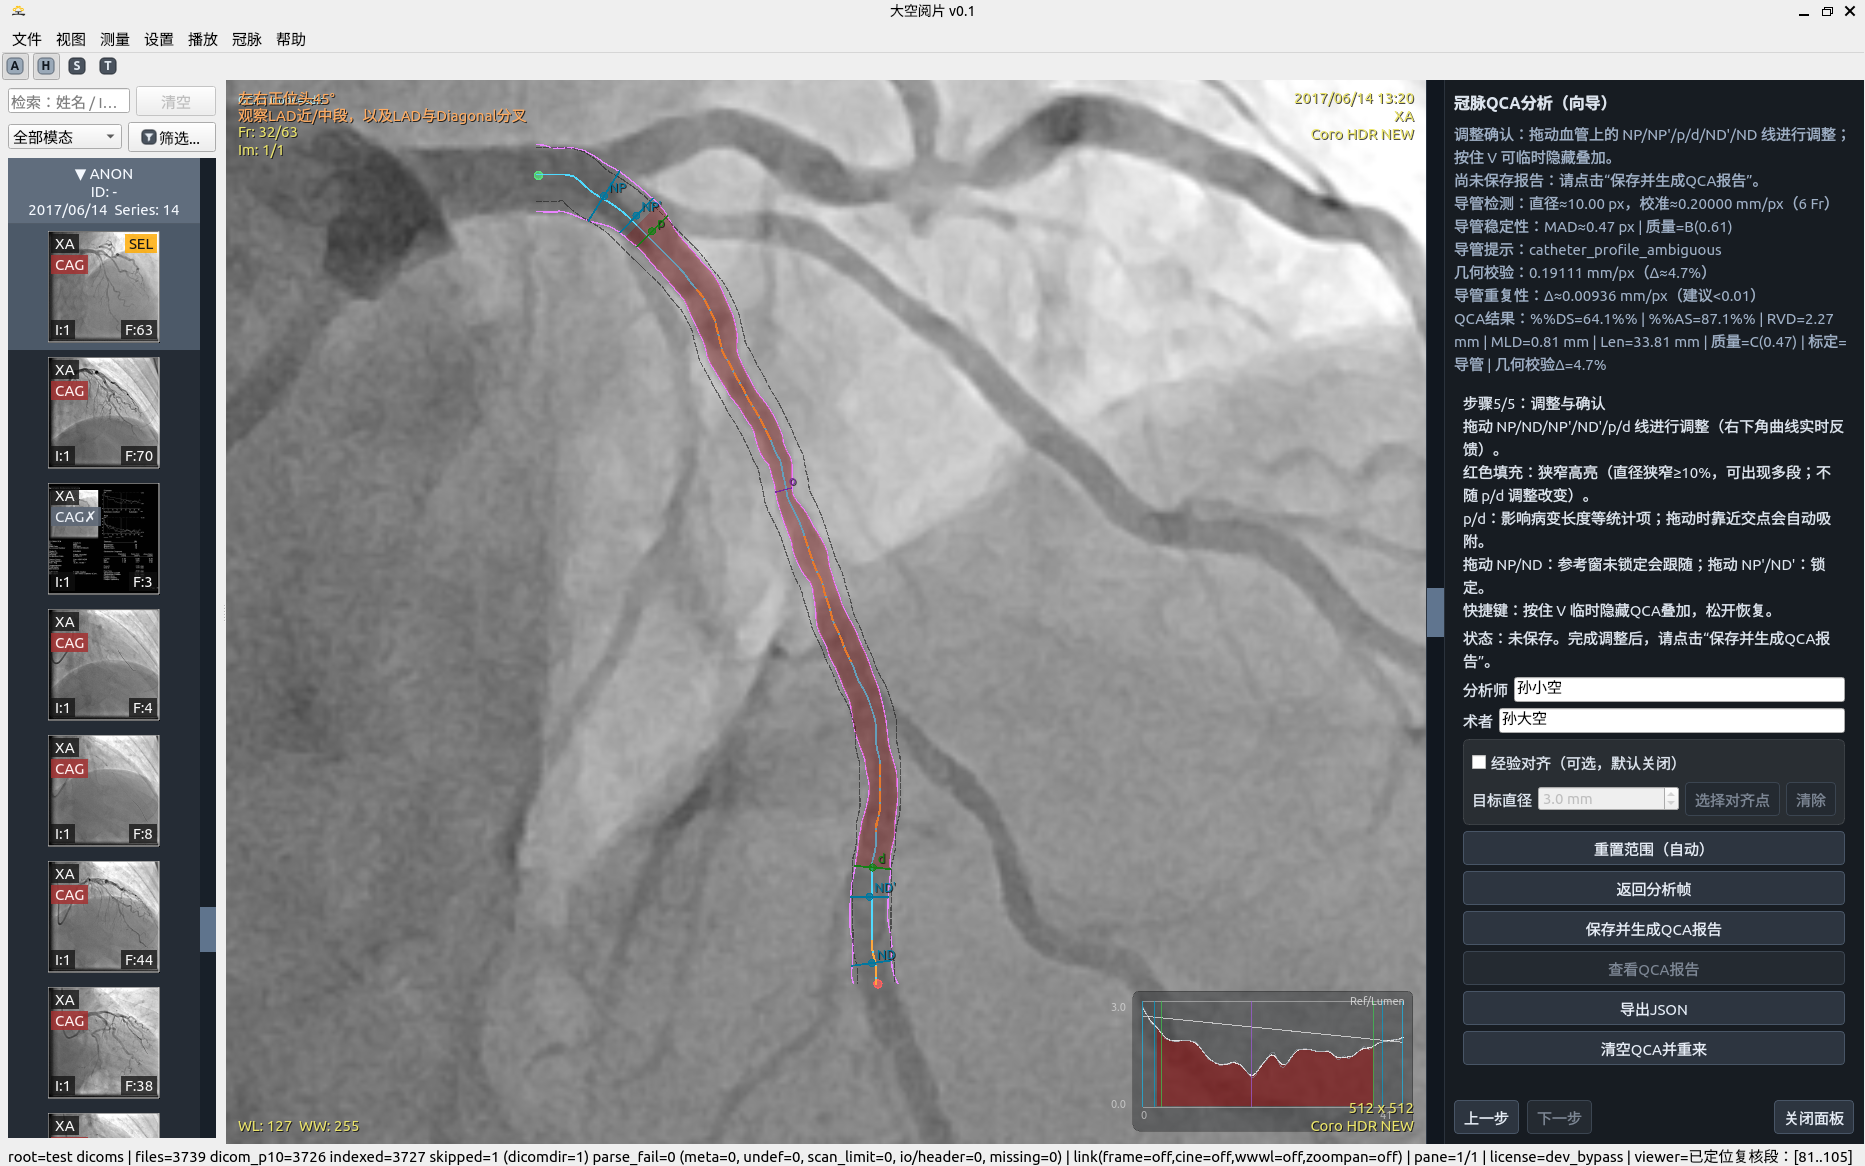

QCA分析及调整

QCA 分析步骤 7

5. 冠脉 QCA 分析

半自动流程强调“可解释 + 可修正 + 可重算”,而非一次性黑盒输出。

• 导管标定:拉直空间剖面 + 左右联合动态规划(DP)+ 亚像素修正。

• 边缘检测:极性自适应 + 有符号边缘特征 + 联合状态 DP + 多峰歧义度。

• 稳健性:MAD 统计、质量等级、结构化告警与恢复建议。

• 几何交叉校验:SID/SOD/ERMF/像素间距参与比例复核。